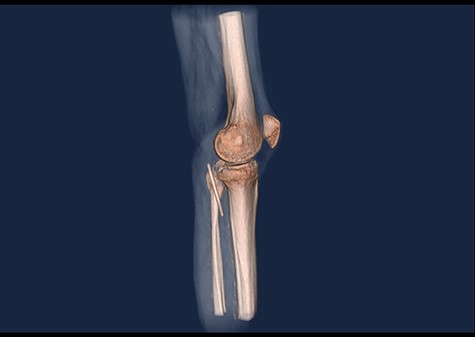

A 61-year-old male patient was diagnosed with inoperable stomach cancer. A TIVAD of the type Braun Celsite ST301® was inserted in the right subclavian vein for administration of chemotherapy. Location was confirmed by chest X-ray and the TIVAD was reported functioning with good backflow (Fig. 1). During initiation of the chemotherapy treatment, the TIVAD was reported malfunctioning. Contrast X-ray showed fibrin sheaths at the distal end of the catheter. An endovascular procedure was performed by an interventional radiologist and fibrin sheaths were mechanically removed with a snare (Fig. 2). Intraoperative X-ray with contrast showed normal contrast accumulation distal to the catheter tip and the patient received the first dose of chemotherapy. One month later the patient was hospitalized with bilateral pulmonary thromboembolism. The patient was treated with low-molecular-weight-heparin and discharged. The chemotherapy treatment continued as scheduled, with one pause due to a fracture of the right humerus after a fall. Occasionally, the TIVAD was malfunctioning and medication was administered using a peripheral venous catheter. During a planned pause in treatment, the patient sought hospital care due to worsening of his general condition. CT showed progress of malignancy and another round of chemotherapy was initiated and administrated using the TIVAD without any problems. Less than a week after, the patient reported feeling a tender swelling underneath his left foot. Ultrasound showed no DVT. The swelling and tenderness disappeared spontaneously, but the patient reported brief incidents of pain under his left foot. A CT scan was performed the next time the TIVAD did not function, showing that the distal 8 cm of the catheter was missing. The patient had no symptoms and reported no discomfort of any kind. The TIVAD was removed, confirming a fracture. A chest CT showed no foreign bodies. A full-body CT scan without contrast was performed, revealing the missing catheter part located at the level of the left knee (Figs 3 and 4). Vascular surgeons performed an endovascular procedure through the femoral vein assuming the catheter had embolized to the popliteal vein. Contrast examination revealed no catheter in the vein and another approach through the femoral artery was made, where contrast imaging shows that the catheter was, in fact, located in the popliteal artery (Fig. 5). The catheter, measuring 7.5 cm, was successfully removed with the use of a snare without any complications. The patient was discharged from hospital and referred to a diagnostic echocardiogram (Fig. 6). A bubble echocardiogram was performed to detect an atrial septal defect but was unsuccessful in doing so. For a final diagnosis, the patient was recommended a transesophageal echocardiogram, but as the diagnosis would not alter the course of treatment, the patient declined further examinations. Except for the reported episodes of pain and swelling of the left foot, the patient suffered no injury and finished his chemotherapy treatment.

3D CT scan showing posteroanterior view with catheter embolus in the level of the left knee.